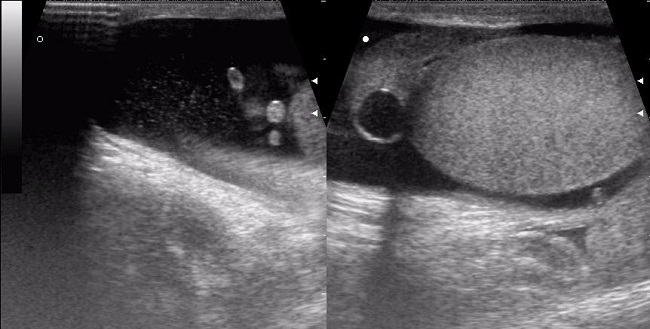

Перекрут гидатиды яичка, или торсия яичка, представляет собой редкое заболевание, при котором происходит внезапное вращение кисты гидатиды яичка вокруг своей оси, что может привести к нарушению кровоснабжения яичка.